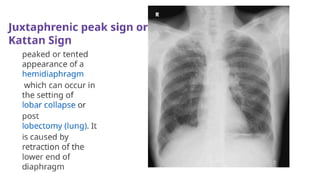

Signs of atelectasis/collapse on x ray

● Homogenous lung opacification

● Displacement of interlobar fissure towards

the atelectasis

● Mediastinal shift towards atelectasis

● Hilum and ipsilateral hemidiaphragm

elevation (peaked appearance)

● Compensatory hyperinflation

● Ribs crowding